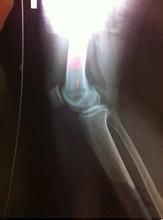

骨质增生是人体衰老的自然现象。随着年龄的增长,一般到了三十五岁以后,人体的骨骼就会发生不同程度的退行性改变,但大部分人无明显症状或体症。

长期、过度、剧烈的运动或活动是诱发骨质增生的基本原因之一。尤其对于持重关节(如膝关节、髋关节),过度的运动使关节面受力加大,磨损加剧。长期剧烈运动还可使骨骼及周围软组织过度地受力及牵拉,造成局部软组织的损伤和骨髂上受力不均,从而导致骨质增生。>>>患上骨质增生怎么办?能不能治疗?

关节损伤包括软组织损伤和骨损伤。关节的骨质增生经常与关节内骨折有直接关系。由于骨折复位不有效,造成关节软骨面不平整,从而产生创伤性关节炎。对于关节内骨折的患者,如果能够及时治疗,作到解剖复位,有效可以避免创伤性关节炎和关节骨质增生的发生。>>>如果预防不当引起骨质增生危害健康了,该怎么治疗好?点击咨询